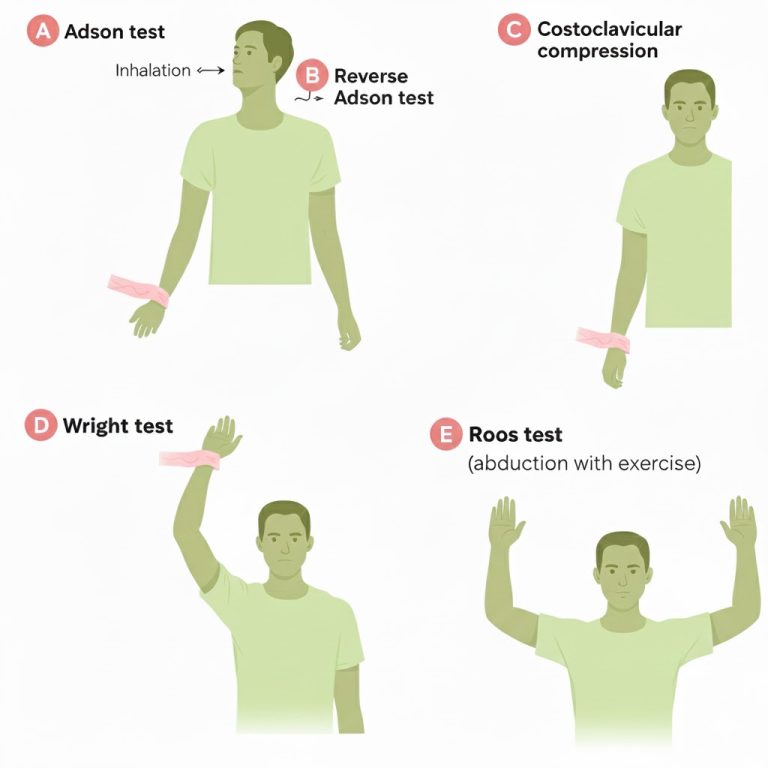

Provocative tests (Adson, Roos/EAST, Wright): why they have limited diagnostic value

Adson test: the patient extends the neck and turns the head toward the tested side (often with a deep breath) while the clinician monitors symptoms and sometimes the radial pulse. A “positive” test is usually taken as symptom reproduction (pulse change alone is not reliable).

Roos test (EAST): the patient abducts the shoulders to 90 degrees, externally rotates, flexes elbows to 90 degrees, then repeatedly opens and closes the hands for up to 1–3 minutes. A “positive” test is typical symptom reproduction (pain, tingling, fatigue, heaviness) rather than simple discomfort.

Wright (hyperabduction) test: the arm is elevated and externally rotated (hyperabducted) while monitoring symptoms and sometimes pulse changes; it may provoke symptoms in those who compress structures under the coracoid/pectoralis minor region.

Why these tests are not definitive: many healthy people can develop pulse changes, numbness, or discomfort with sustained overhead positions; results depend on posture, effort, shoulder mobility, anxiety, and examiner technique. These tests can be supportive when they match the full clinical picture, but they should not “diagnose TOS” in isolation.